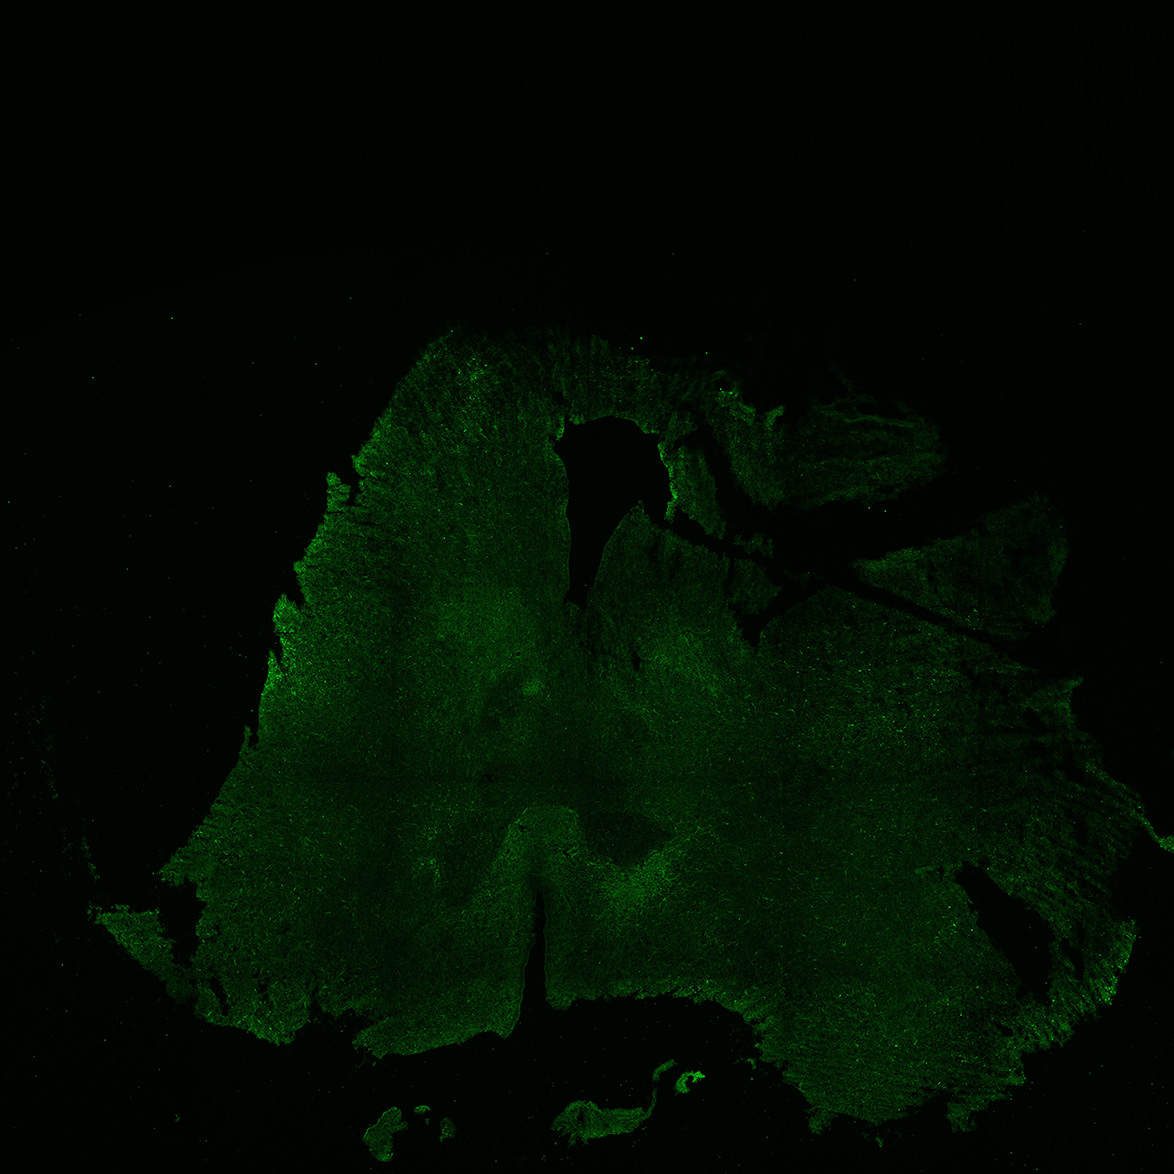

An anatomical analysis of the developing human midbrain from 6 post-conceptional weeks (PCW) to 22 PCW reveals increased tissue complexity, characterized by the emergence of dopaminergic nuclei, as highlighted by immunofluorescence analysis for tyrosine hydroxylase (TH).

17PCW

17PCW human midbrain